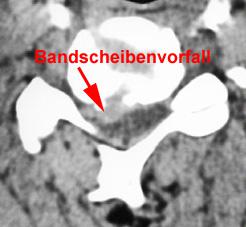

Der klassische oder Idealfall ist ein Bandscheibenvorfall in einer Höhe. Jedoch treten manchmal Bandscheibenvorfälle in 2 Höhen gleichzeitig auf. Eine große Ausnahme sind Bandscheibenvorfälle in 3 Höhen. Auch bei diesen Ausnahmefällen können - wenn bestimmte Voraussetzungen gegeben sind - Bandscheibenprothesen in mehreren Höhen implantiert werden. Wichtig ist, dass eine gute Beweglichkeit der Wirbelsäule vorliegt, die Bandscheibe noch eine ausreichende Höhe hat und die Verschleisserscheinungen begrenzt sind.